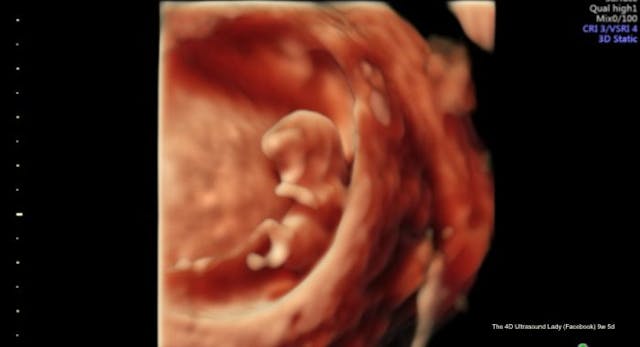

Of course, a child shredded by a suction aspiration abortion will look like quite different from this:

“Once you get to like 10-12 weeks, it’s like see-through because it doesn’t have like — bone hasn’t finished forming, but you can start to make out little hands and little feet,” said Rubino.

In the video, Rubino spoke about seeing the “little hands and little feet” of preborn babies after she suctions them out of their mothers, killing them.